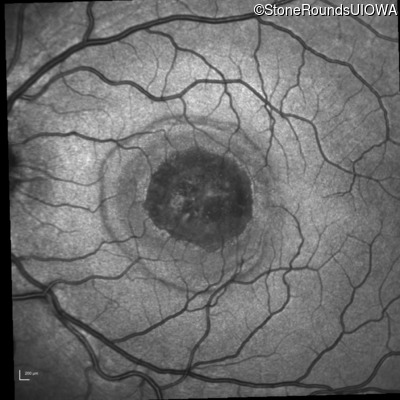

Infrared Fundus Photograph - Right - 20/40 -2

Exemplar